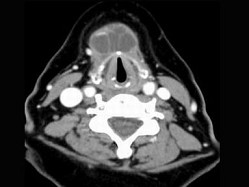

10.CT檢查結果如下,患者的最可能的診斷為  (    )

正確答案:9.A;10.C;11.D